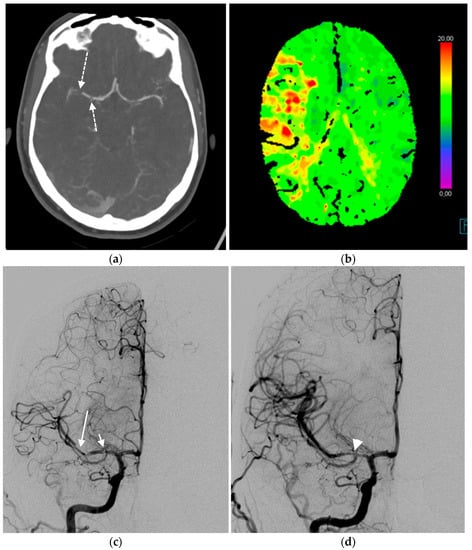

2.2. Ischemic Disease